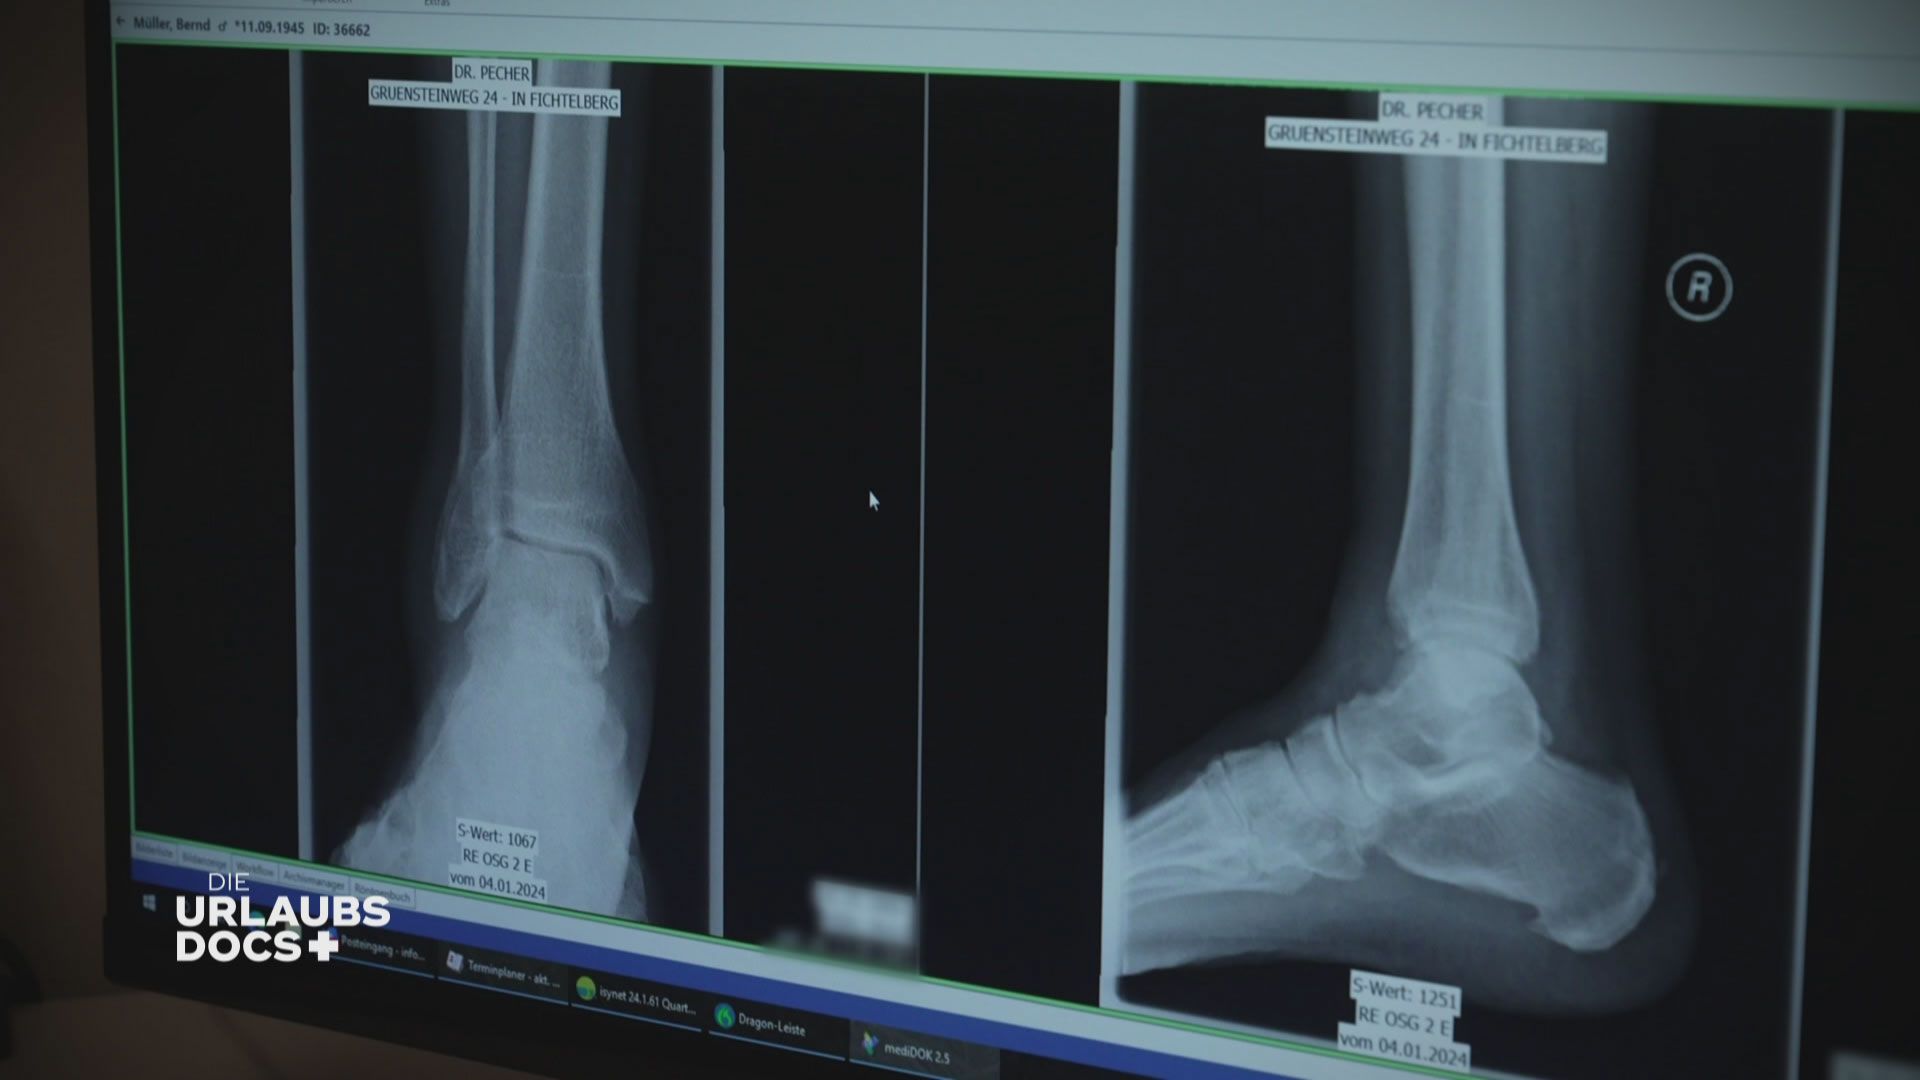

Folge 3: Fichtelberg: Patient mit Knöchelbruch